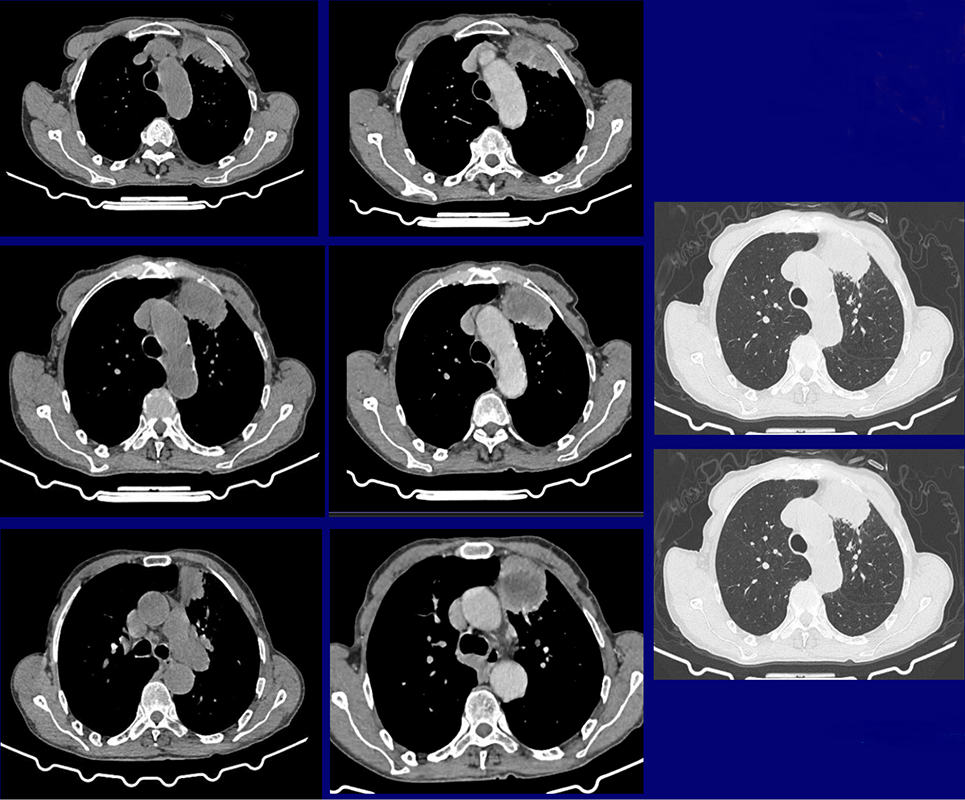

Homme de 79 ans, Ancien tabagique, sevré il y a 18 ans.

Présente depuis 6 mois une hémoptysie intermittente

Sans autres signes respiratoires dans un contexte d'apyrexie et d'asthénie

4 / 5

QUEL EST VOTRE DIAGNOSTIC ?

A – A-TUMEUR BRONCHIQUE

B – ABCÈS

C – KYSTE HYDATIQUE

D – PNEUMOPATHIE

E – ATTEINTE TUBERCULEUSE